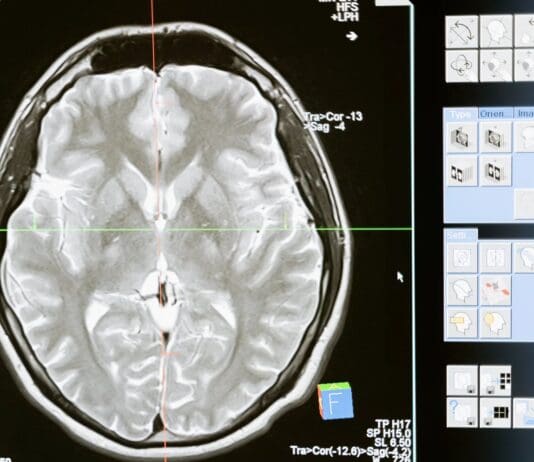

Recently released data has highlighted the scale of radiology-related clinical negligence claims within the NHS, underscoring the mounting strain on diagnostic services nationwide.